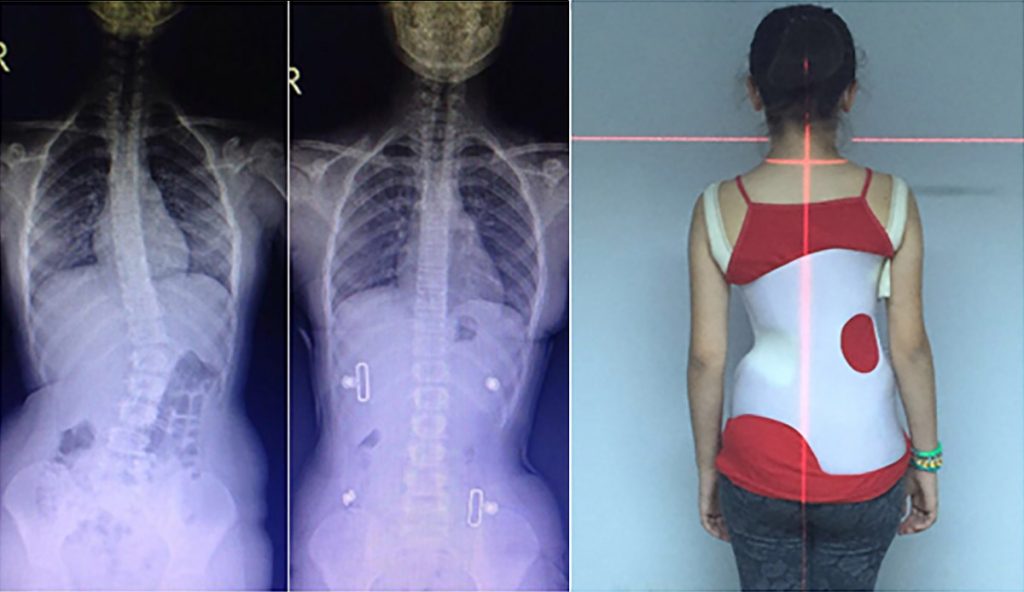

KORSE ÖNCESİ - SONRASI 1

korseler-1

KORSE ÖNCESİ - SONRASI 2

korseler-2